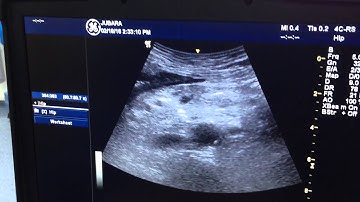

ULTRASOUND GUIDED CELIAC PLEXUS BLOCK : ANTERIOR APPROACH